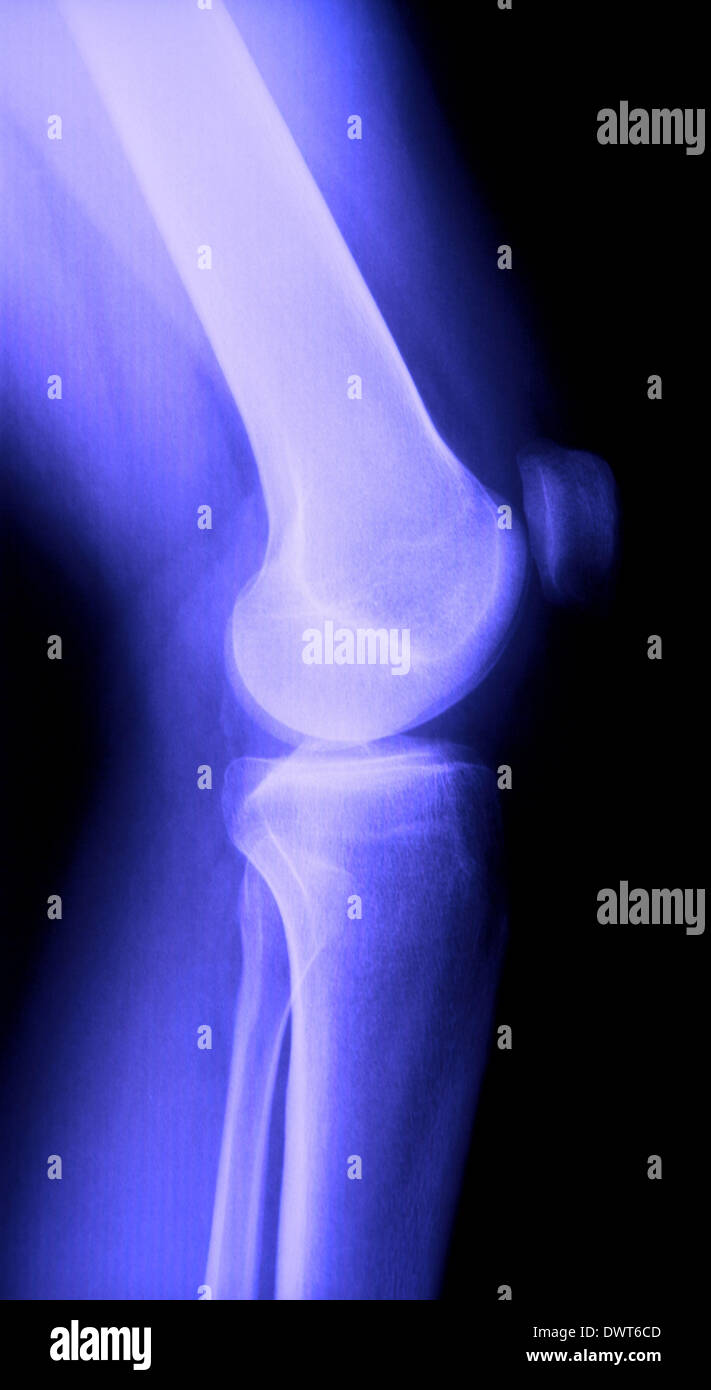

Lateral Xray Of The Knee By Medical Body Scans ubicaciondepersonas What Will Show Up On A Knee X Ray Typically, the cartilage in one compartment of the joint (that is, the medial, lateral, or anterior patellofemoral joint compartment) is most severely affected. Detect fractures, osteoarthritis, and bone diseases. Evaluate the condition of the joint space, indicating. A person may start to notice stiffness and joint pain , especially after resting for a while. It’s fairly clear that it’s the. What Will Show Up On A Knee X Ray.